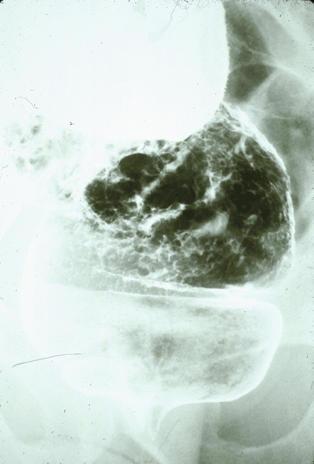

症例提示(所在地,施設名等): 東京都・ 国立がんセンター中央病院と九州がんセンターの共同作成

TIC症例

症例登録日 2000/01/18

画像数 23

性別 男性

年齢 75-79

画像ID:1550

[ 画像ID:1550 ]

■詳細データ

部位(臓器別)大腸/S状

検査方法X-P

病変の最大径(ミリ)40以上

腫瘍の深達度mp

多発腫瘍(同一臓器)

多重腫瘍(他臓器)